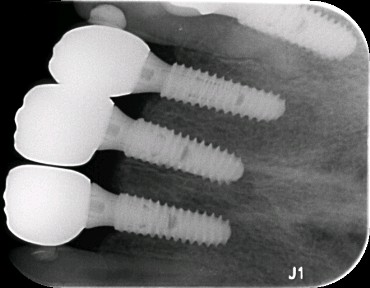

向患者交代病情、治疗计划、费用、预后等,患者知情并同意治疗。,抽静脉血20ml,12植入欧美 hiossen 种植体3.5*11.5mm,11.21植入欧美 hiossen 种植体4.0*11.5mm上覆盖螺丝,颊侧骨缺损区植入人工骨粉 傲骨0.5g及 CGF ,并盖百傲膜及 CGF 膜,严密缝和。二期三期如期进行与近日佩戴牙齿。

术中